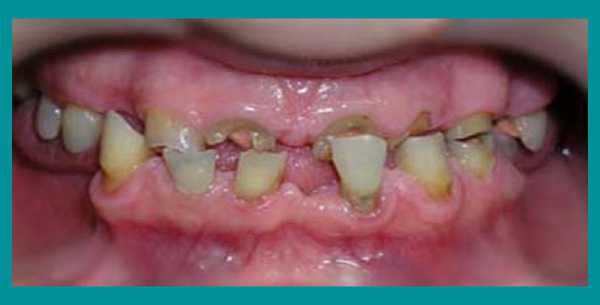

Трудности с пережевыванием пищи, отсутствие зубов, недовольство своим внешним видом, невозможностью улыбаться окружающим - вот неполный перечень тех жалоб, с которыми пациентка обратилась за стоматологической помощью. Из опроса выяснилось, что из-за страха перед лечением визит к стоматологу откладывался надолго, а точнее - на 31 год…

Осмотр выявил очень сильную горизонтальную стираемость верхних и нижних зубов, снижение высоты прикуса и изменение его из нормального в обратный (нижние зубы при смыкании находились впереди верхних). Одновременно на ортопантомограмме височно-нижнечелюстного сустава определялся двухсторонний подвывих нижней челюсти.